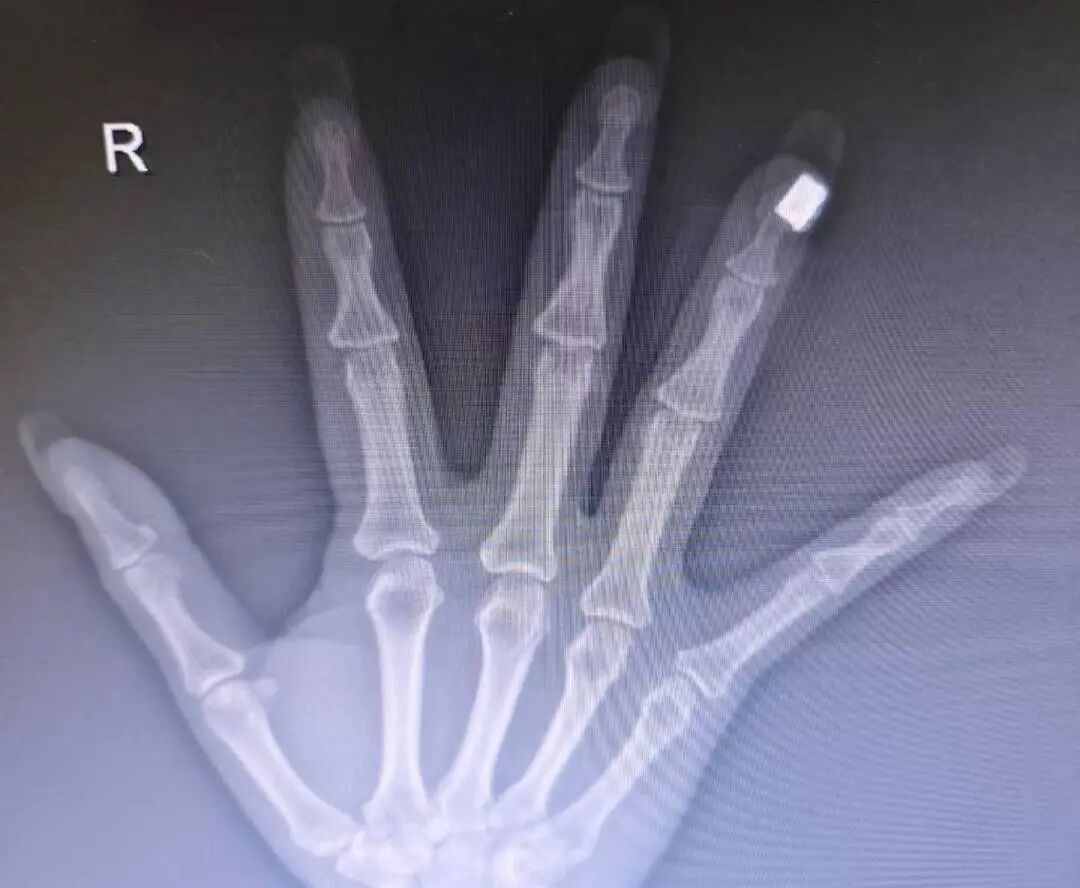

“有一次我在急診接診一位手外傷患者,給她拍手部X光時,意外發現美甲區域出現了高密度影,這說明美甲里面含有金屬成分。”醫生仔細觀察后發現,患者的美甲上裝飾有珠子或類似鉆石的點綴,“外表看起來像是塑料或人造鉆,但內核應該含有金屬成分。”

該醫生此前遇到的案例

他表示,核磁共振檢查嚴禁攜帶任何金屬物品。如果美甲飾品中含有鐵磁性金屬,在強磁場下可能被吸走,不僅可能傷及患者手指,還可能損壞昂貴的醫療設備。“問題是,很多做美甲的人可能并不清楚自己指甲上的裝飾品是否含金屬成分。”